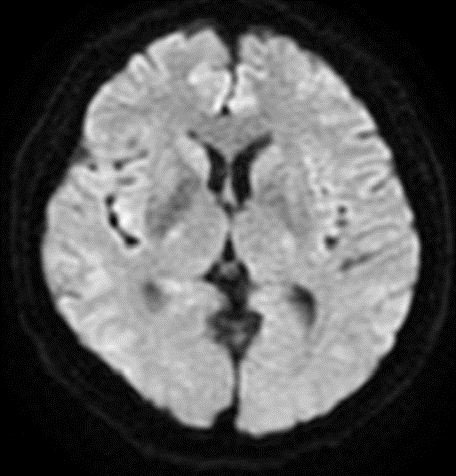

颅脑MRI

波科支架怎么样径技-弓上病例大赏|第205期·放疗后症状性颈动脉狭窄支架置入治疗一例_https://www.jmylbn.com_新闻资讯_第3张

波科支架怎么样径技-弓上病例大赏|第205期·放疗后症状性颈动脉狭窄支架置入治疗一例_https://www.jmylbn.com_新闻资讯_第4张